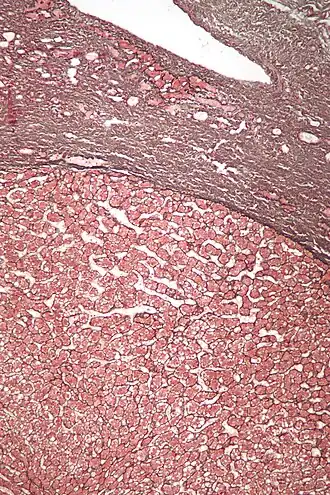

![]() Micrografía de un adenoma hepático (base de la imagen). Tinción hematoxilina-eosina | ||

Los adenomas hepáticos son, típicamente, nódulos bien circumscriptos que constan de hojas hepatocitarias con un citoplasma vacuolado de aspecto burbujeante. Los hepatocitos se disponen en un armazón de reticulina regular y más o menos igual a tres células de espesor.

El diagnóstico histológico de los adenomas hepáticos puede ser facilitado por la impregnación argéntica (tinción con sales de plata). En los adenomas hepáticos, el armazón de reticulina y los hepatocitos no forman capas de cuatro o más hepatocitos, como se ve en el carcinoma hepatocelular.

Las células parecen hepatocitos normales y son recorridos por vasos sanguíneos pero carecen de espacios porta y venas centrales.

Micrografía de adenoma hepático. Tinción hematoxilina-eosina. -